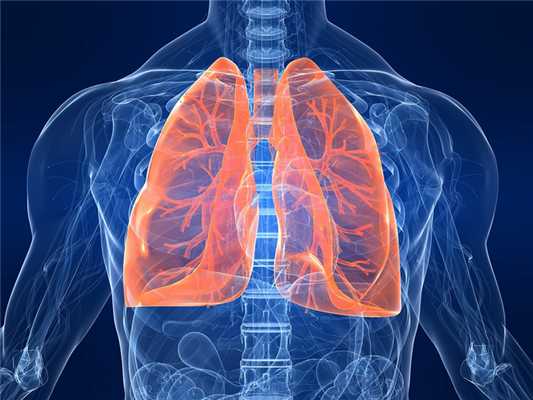

Легкое - это один из парных, самый объемный орган человека. В здоровом состоянии он розово-красного цвета, структура - мягкая, губчатая.

Расположение легких

Легкие располагаются посередине грудной клетки. Их защищает и поддерживает каркас из ребер, по 12 слева и справа. Со стороны спины органы защищаются позвоночным столбом.

Для обеспечения возможности дышать между ребрами присутствует мышечная ткань, к грудине кости фиксируются хрящами. Со стороны спины легкие располагаются на 2-3 см выше ключиц.

Снизу орган граничит с диафрагмой, разграничивающей брюшину и грудную клетку. С правой стороны под легким расположена печень. С левой стороны сверху примыкает сердце, а снизу - частично желудок. Точное расположение легких у человека наглядно можно посмотреть на фото.

Какое строение имеют легкие человека

Органы по форме похожи на полуконусы, но не являются идентичными по форме и размеру. Легкое, расположенное справа, покороче и пошире левого, а также более крупное. Это объясняется тем, что справа расположена печень. В легком, расположенном слева, имеется врезка для прилегания сердца. Орган, расположенный справа имеет три доли: нижнюю, среднюю и верхнюю. Левое имеет только две доли: верхнюю и нижнюю. Каждая доля имеет сегменты, которые снабжаются крупным кровеносным и дыхательным сосудом.